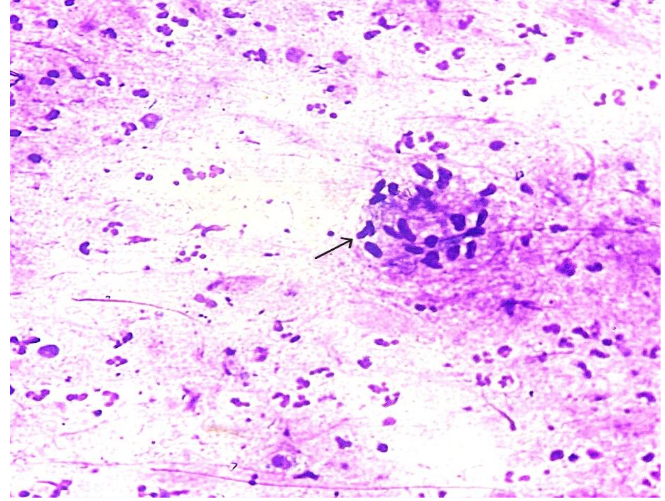

On clinical examination, the patient had a soft to firm swelling in the dorsum of right hand of size 3 x 3 cm. Clinical diagnosis was ganglion cyst or lipoma. There was no associated lymphadenopathy or systemic signs of infection such as fever. Routine laboratory tests, including complete blood count (CBC), liver and renal function tests, and chest X-ray, were all unremarkable. FNA Cytology of the lesion was performed using a 22-gauge needle and about 1.5 ml of pus was aspirated. Air dried and alcohol fixed smears were made and the material was sent to microbiology for culture and sensitivity and also for fungal culture. FNAC smears were moderately cellular and showed epithelioid granulomas and plenty of scattered, degenerated neutrophils and histiocytes with few characteristic acute angle branching and septate fungal hyphae and fungal spores as well, suggestive of an Aspergillus species.

When present, cutaneous swellings are readily accessible to FNAC. When collected, sufficient and representative cytological material can consistently provide a diagnosis. On the basis of morphology, Aspergillus and Mucor are easily distinguished from one another. Mucor is distinguished by wide, non-septate hyphae that branch at a right angle. In this case, patient is old-aged, immunocompetent and identified with fungal elements on FNAC. In instances of Cutaneous Aspergillus, species identification is crucial. The most prevalent kind found in India is A. flavus. Species identification has epidemiological relevance since it varies on different geographic regions, which helps with diagnosis in challenging situations, but it is not very significant to patient care.

Narrow septate hyphae with acute-angle branching is seen in tissue sections of our case, particularly when special stains are used (PAS and GMS). In our case, cytological examination is pivotal in identifying Aspergillus species, followed by biopsy with fungal stains confirmed the diagnosis.